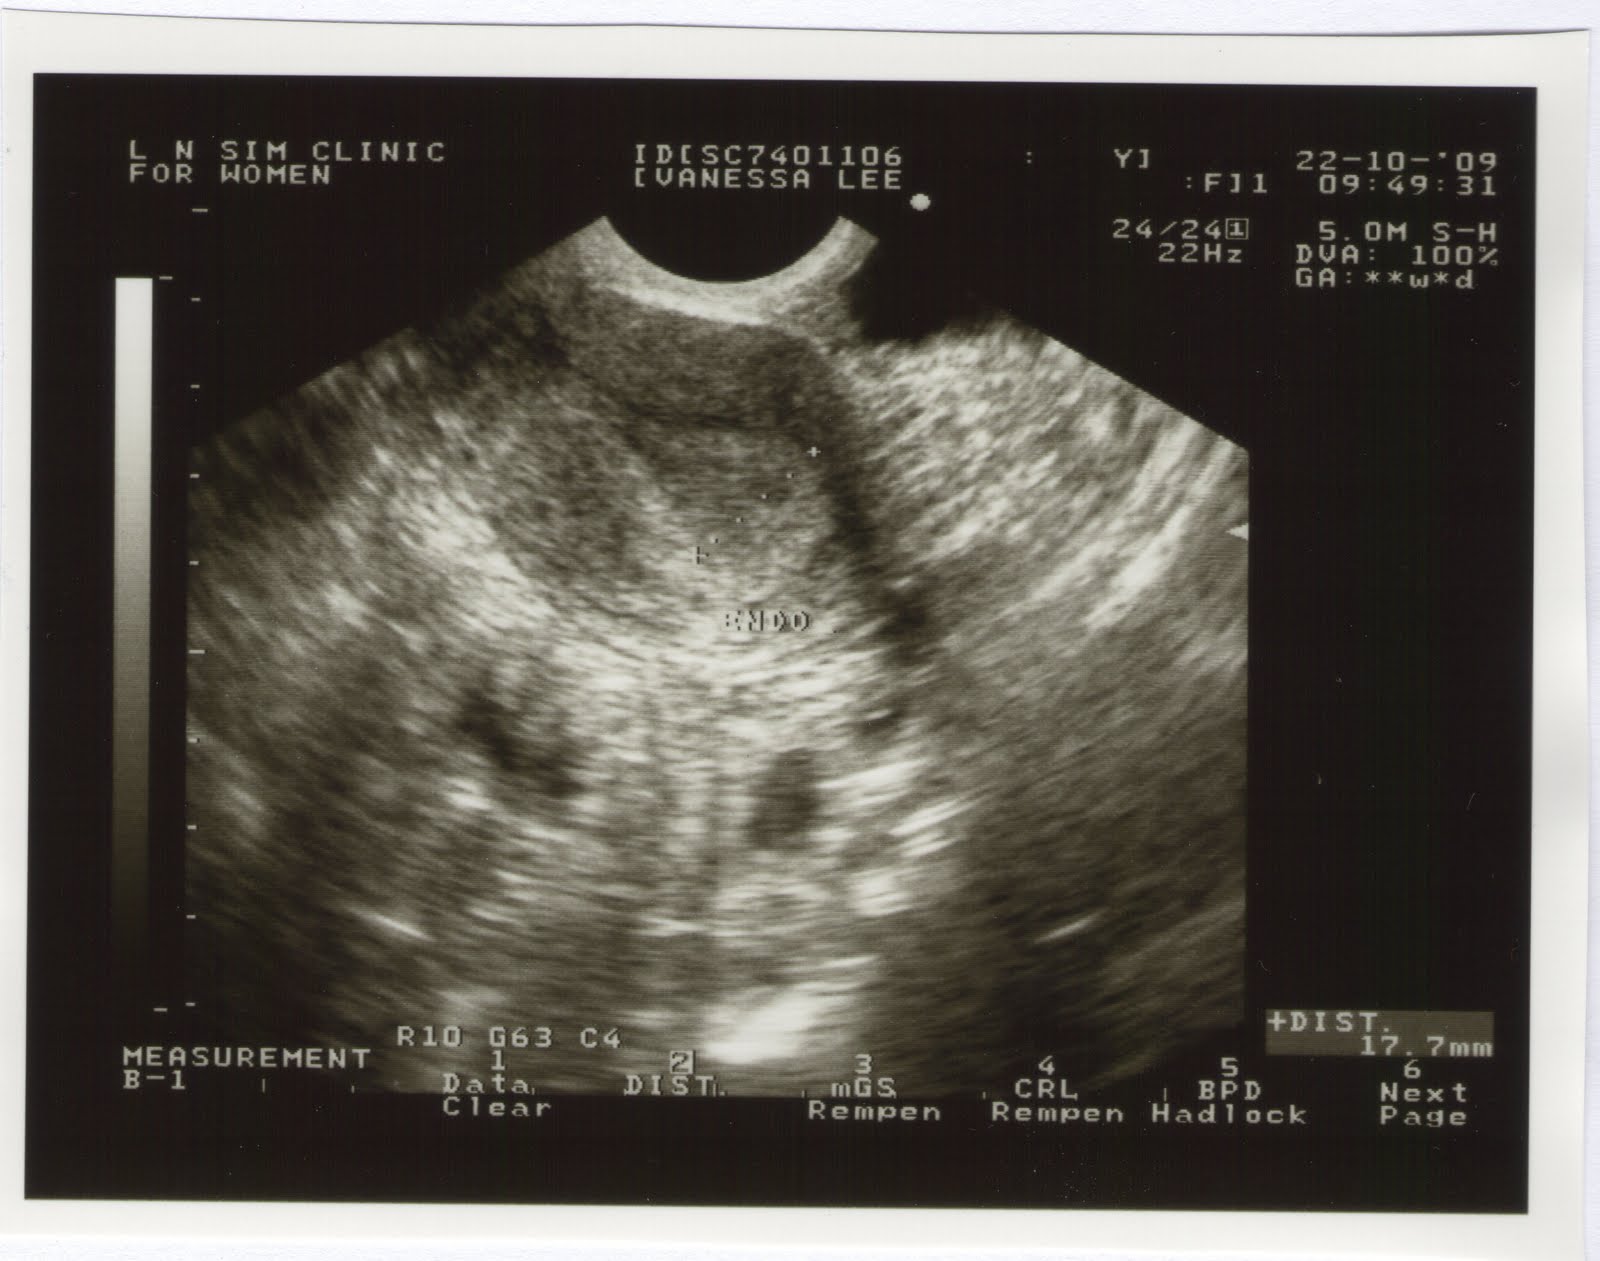

10am. Had called the clinic earlier to ask about going in to the clinic to do a check on B. Went to Dr Sim's clinic. Baby was ok. He was moving alot, again. His heartbeat was also ok. But Dr Sim asked if we want to move the c-section earlier to today.